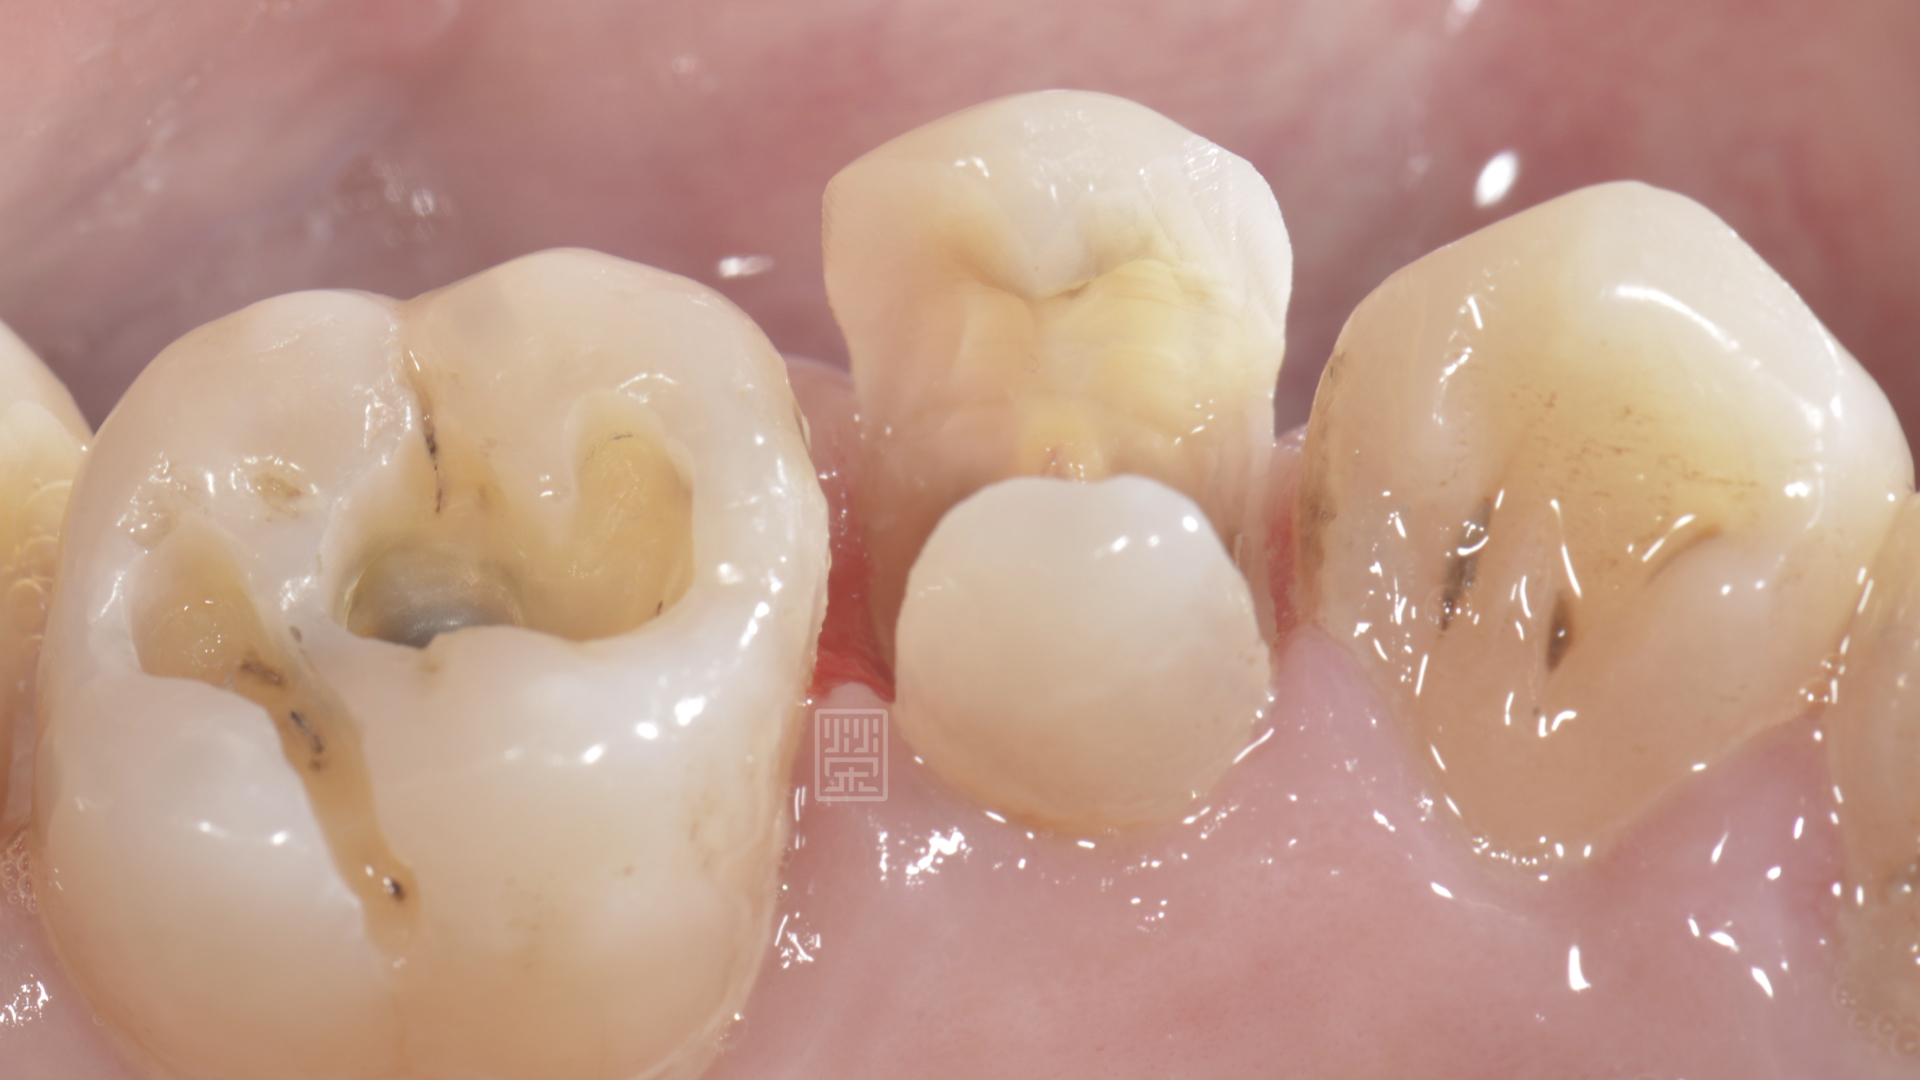

利用黏著式嵌體對牙齒只需做最少的修磨,但是在頰側,為了有好的外觀,所以包覆到牙齦邊緣,空間厚度以最小厚度0.3毫米為製作空間,減少對牙齒的傷害,完成全瓷嵌體後,恢復理想的功能與美觀,也利用全瓷嵌體的特性,保存了牙齒,減少牙齒需要拔牙的可能性。

另一個角度看清除蛀牙後的狀況

全瓷嵌體修復治療完成